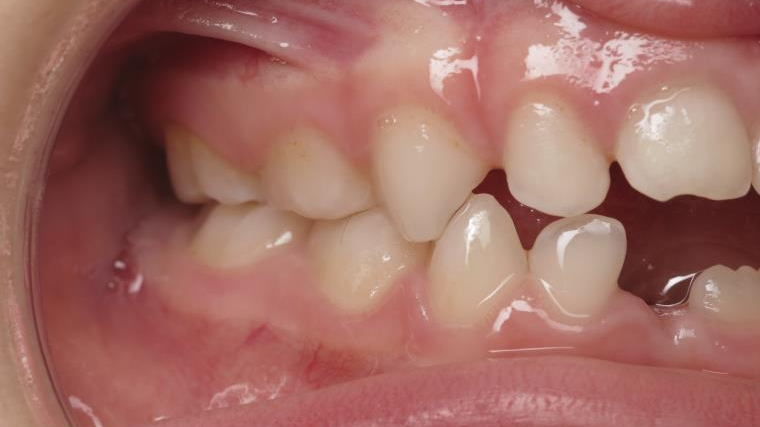

appareillage mobile pendant 14 mois

sectionnel multibagues pendant 8 mois